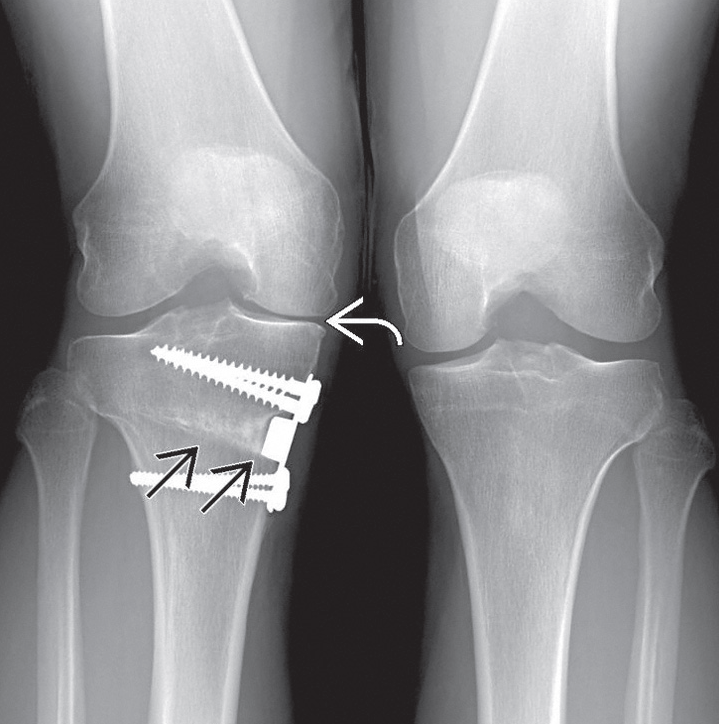

Osteoartrit eğer diz ekleminin mekanik aksındaki bozukluklara bağlı gelişmişse, osteotomi ile eklemde aşınmaya sebep olan aks bozukluğu düzeltmeye çalışılabilir. (Ayrıntılı bilgi için Diz Çevresi Osteotomileri konusuna bakınız)

Diz ekleminin mekanik aksındaki bozukluğun osteotomi ile düzeltilmesi